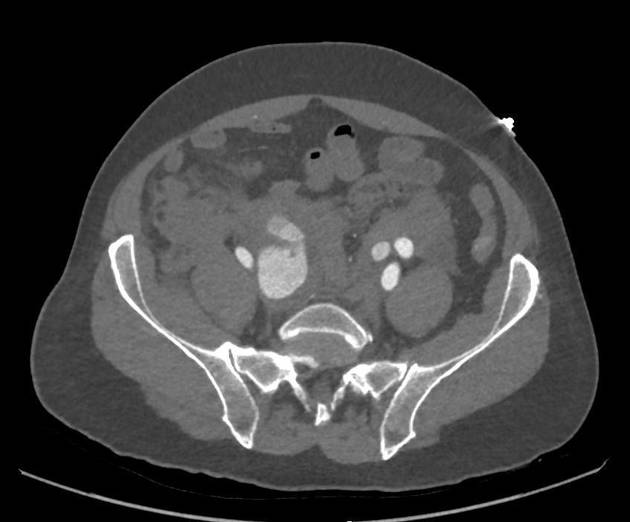

Point-of-care ultrasound (POCUS) is a common first-line tool used in emergency departments. Its convenience and high sensitivity in detecting conditions like abdominal aortic aneurysms make it a super important diagnostic method. However, when it comes to internal iliac artery aneurysms, POCUS can miss the diagnosis because of the deep anatomical location of the affected vessel and sometimes, the overlying bowel gas muddles the picture.

This is where contrast-enhanced computed tomography (CT) scans prove their worth. In the case addressed, after initial tests failed to capture the full extent of the aneurysm, a CT scan confirmed the presence of a sizable ruptured aneurysm. The CT scan not only revealed a large aneurysm but also gave a clear map of the surrounding area by detecting a retroperitoneal hemorrhage and pinpointing potential bleeding sites.

Therefore, while basic ultrasounds are a key first step, CT scans work as a must-have advanced diagnostic tool and are critical when initial imaging does not resolve the patient’s condition.